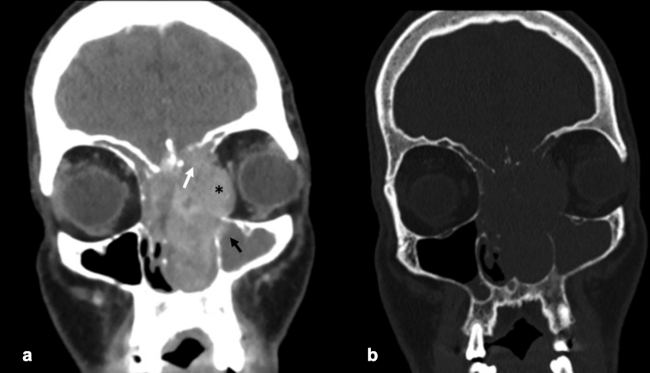

La TC de corte fino (espesor de corte de 1 mm) con reconstrucciones en plano coronal y sagital, es la mejor prueba de imagen inicial para el estudio del NBO. En la TC, aparece como una masa homogénea de tejido blando en la bóveda nasal con realce moderado y uniforme (►Figs.1y2). Se pueden encontrar calcificaciones punteadas dispersas (►Figs.2,3,4,5a,6).50 El valor principal de la TC es una mejor definición de la afectación ósea en comparación con la RM. La TC ayuda a evaluar la erosión ósea de la placa cribiforme, la fóvea etmoidal y la lámina papirácea (►Figs.1,2,3,4,5a,8). Sin embargo, la remodelación ósea sin erosión puede presentarse en algunos casos debido a su patrón de crecimiento indolente.3,35,49 Los estudios de TC generalmente revelan un patrón lítico y muy raramente hiperostosis dominante que simula displasia fibrosa.51 La TC también es útil para evaluar la presencia de metástasis regionales en cuello y a distancia.52,53

La RM es la prueba de imagen de elección para evaluar los detalles de la extensión y la estadificación locorregional del tumor. La RM es superior a la TC para determinar el grado de afectación del tejido blando (►Fig. 9) con una mejor evaluación de la afectación intracraneal (►Figs.10,11,12,13,14), orbital (►Figs.14y15), de la base del cráneo y la invasión perineural.53,54 La RM tiene un valor añadido para distinguir la afectación dural de la del parénquima cerebral (►Fig. 12).55 En la RM, el NBO aparece hipointenso respecto a la sustancia gris en imágenes ponderadas en T1 y de isointenso a hiperintenso en las imágenes ponderadas en T2 (►Figs.10,11,12,13,14,15).56 Muestra un realce homogéneo, excepto en áreas con hemorragia o necrosis. Además, permite diferenciar las secreciones retenidas del tumor, al ser estas hiperintensas ponderadas en T2.53,55 Los hallazgos de imágenes clásicos incluyen una masa “en forma de mancuerna” que se extiende a través de la placa cribiforme (►Fig. 12), con la parte estrecha a nivel de la placa. Los quistes tumorales periféricos (►Figs.5b,12,14,16) y las calcificaciones moteadas son bastante característicos de NBO.1